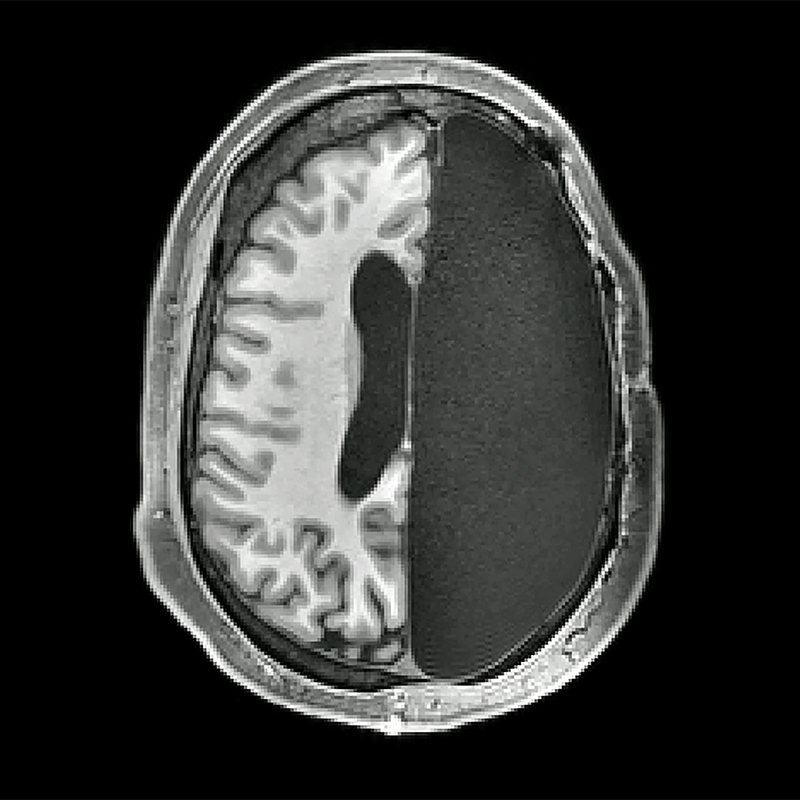

ĐẠI CƯƠNG PHẪU THUẬT ĐỘNG KINH

Đại cương 20% bệnh nhân vẫn bị các cơn động kinh (seizures) cho dù đã được dùng rất nhiều loại thuốc chống động kinh khác nhau. Phẫu thuật có thể giúp kiểm soát được các cơn động kinh ở nhiều bệnh nhân kháng trị. Phẫu thuật thường được chỉ định cho bệnh nhân bị cơn động kinh nặng, vẫn lên cơn cho dù đã dùng đầy đủ thuốc ít nhất […]